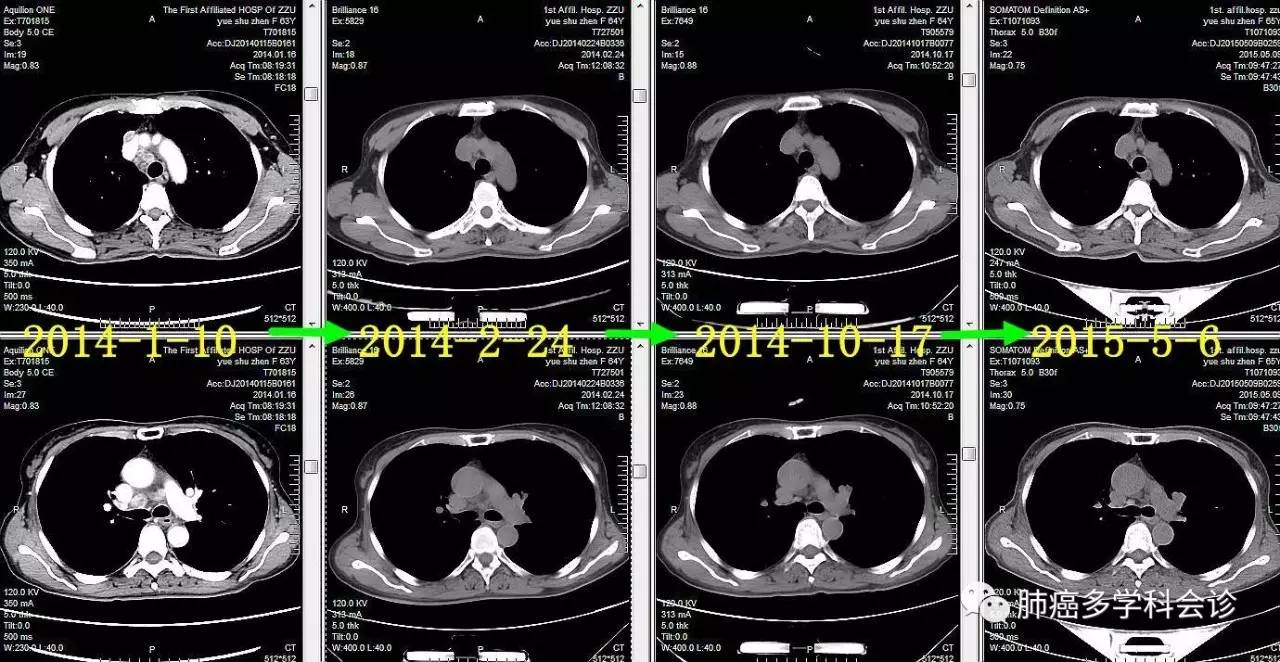

患者岳SZ,女,68岁。2014年1月,因咳嗽吐痰做CT发现左下肺占位、纵隔和双肺门淋巴结肿大;头颅MRI发现左侧额叶转移瘤。SPECT示:左侧第2前肋局部骨代谢异常活跃,结合CT考虑骨折。

●2014.01 ~ 2016.03 口服易瑞沙获部分缓解,服药共2年余后因疾病进展而停用。以下是治疗过程中胸部肿瘤CT图像的变化:

微信图片_20170523115459.jpg

●2015-5 ~ 2015-8,PEM+NDP化疗4周期,PEM单药1周期,进展。